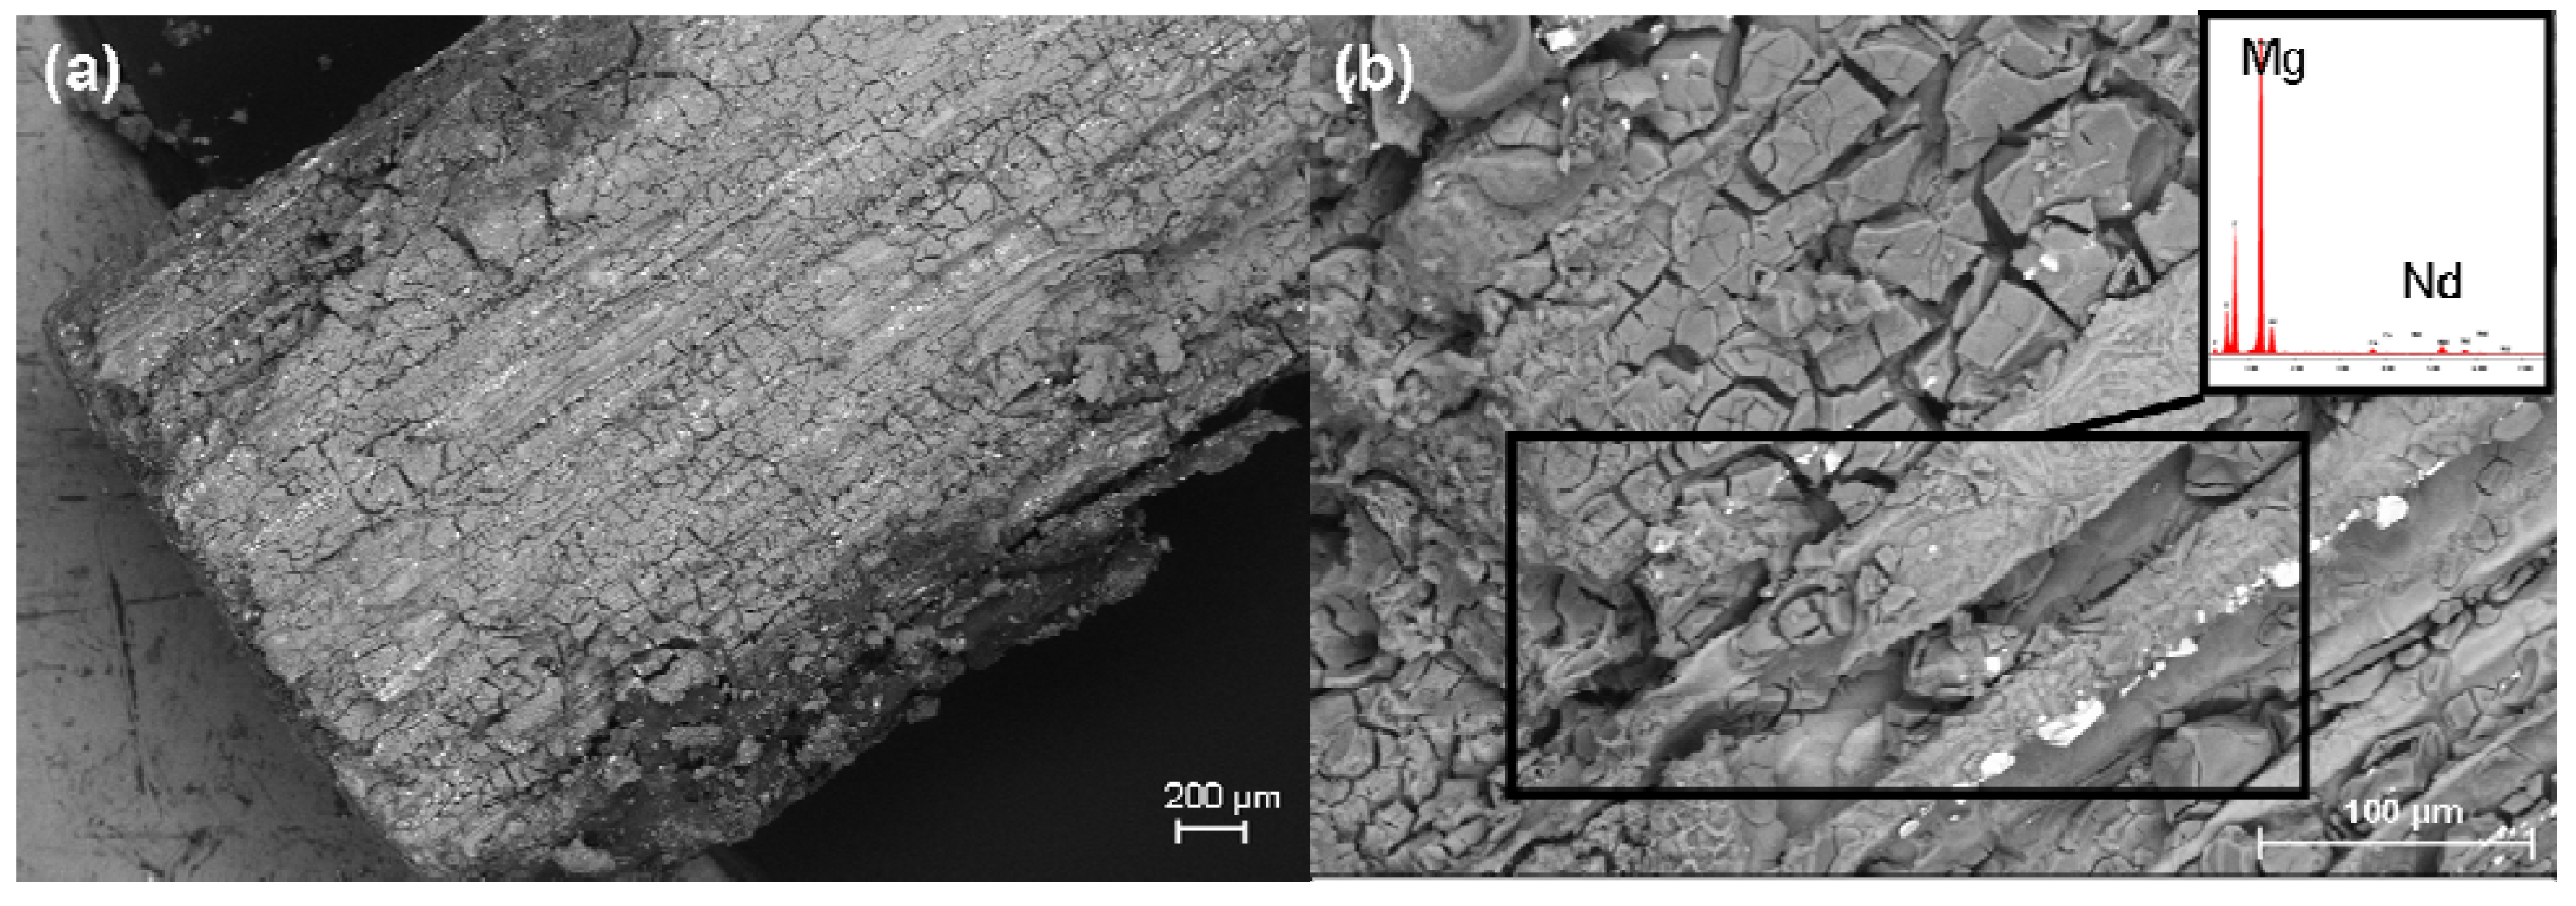

2.6. SEM Investigation and the EDX Analysis

3.3.3. Scanning Electron Microscopy and Energy Dispersive X-Ray Spectroscopy